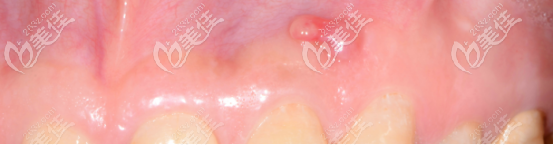

我當時做根管治療的時候根充不到位,從而炎癥再次復發(fā),導致根尖炎,沒過多久牙齦上長了一個小膿包。

(這個膿包并沒有消失)